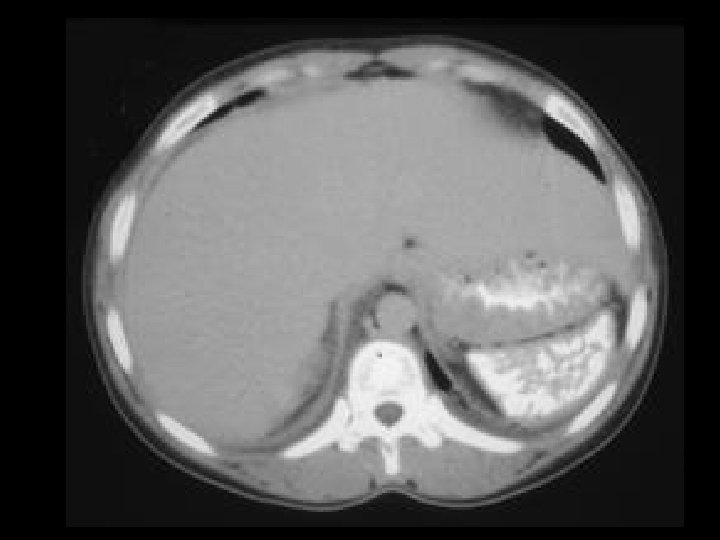

ADPKD • Findings: – Enlarged bilateral kidneys containing innumerable cysts – May also see hepatic cysts – Cysts complicated by hemorrhage or infection – NO increase risk of RCC • ddx: – NONE! – This is an Aunt Minnie!